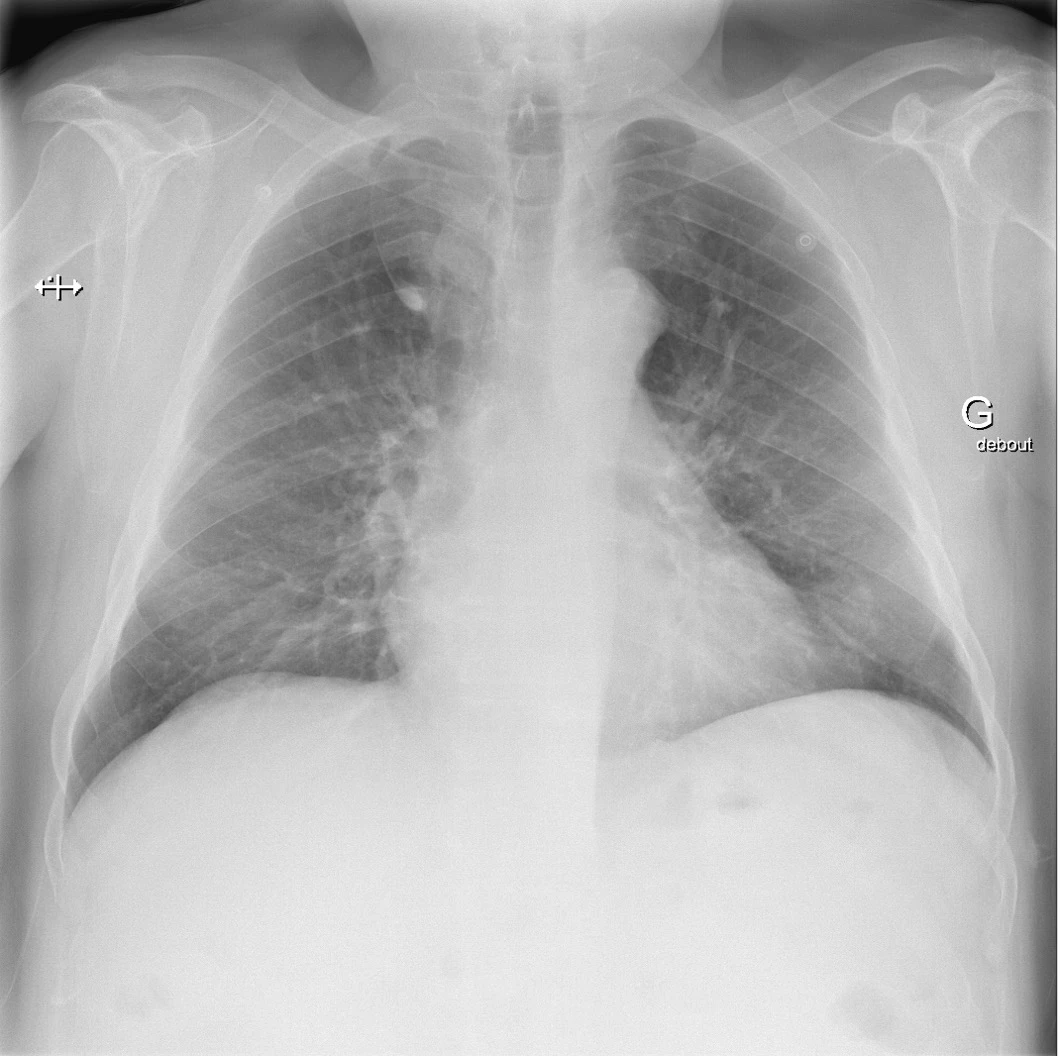

Le lobe azygos est une anomalie congénitale, ou variante anatomique. Bien que rare (il se retrouve chez environ 1% de la population avec un ratio homme : femme de 2 : 1 et sur 0.4 % des radiographies thoraciques), cette variante doit être connue de la ou du clinicien·ne car elle peut être confondue avec un néoplasie pulmonaire, un abcès ou une bulle d’emphysème voir un pneumothorax.

Ce « lobe accessoire » est formé durant l’embryogenèse, par la migration anormale d’une veine précurseur de la veine azygos, dans le segment apical du lobe pulmonaire supérieur droit (beaucoup plus rarement à gauche), au lieu d’une migration dans le médiastin. Cette indentation du lobe supérieur forme le lobe azygos qui lui est adjacent. Le lobe azygos n’est pas à proprement parlé un lobe, mais bien une partie du lobe supérieure. Il n’est pas vascularisé ou ventilé par un système indépendant ou spécifique.